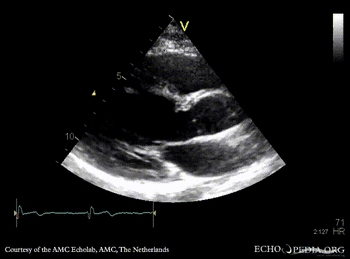

E00729.gif E00730.gif

A3CH: subvalvular membrane A3CH with Color Doppler: high velocity flow in LVOT